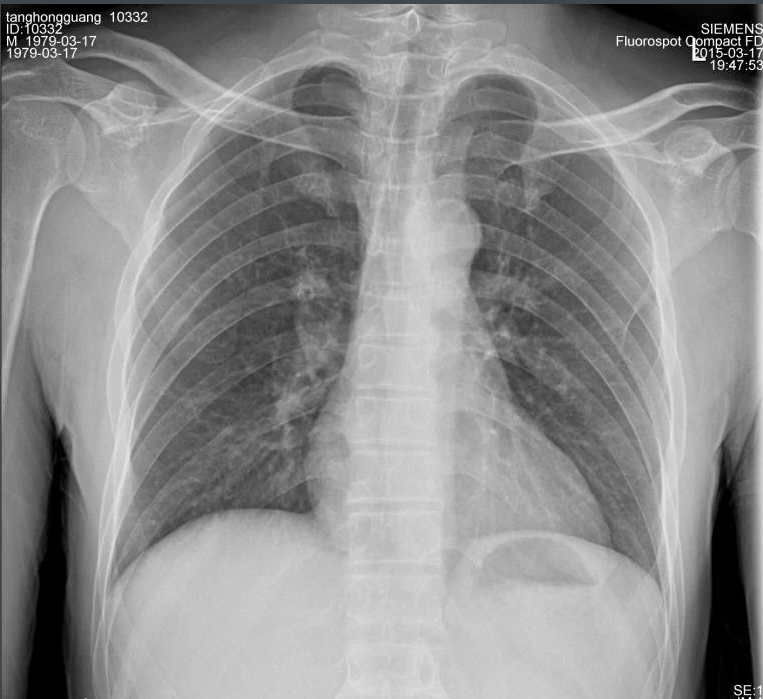

X射線,是一種頻率極高,波長極短、能量很大的電磁波。具有穿透性,但人體組織間有密度和厚度的差異,當X射線透過人體不同組織時,被吸收的程度不同,經(jīng)過顯像處理后即可得到不同的影像。下面那我們來聊一聊關(guān)于X射線的三大特性分別是哪些。

X射線因其波長短,能量大,照在物質(zhì)上時,僅一部分被物質(zhì)所吸收,大部分經(jīng)由原子間隙而透過,表現(xiàn)出很強的穿透能力。X射線穿透物質(zhì)的能力與X射線光子的能量有關(guān),X射線的波長越短,光子的能量越大,穿透力越強。X射線的穿透力也與物質(zhì)密度有關(guān),利用差別吸收這種性質(zhì)可以把密度不同的物質(zhì)區(qū)分開來 。

X射線同可見光一樣能使膠片感光。膠片感光的強弱與X射線量成正比,當X射線通過人體時,因人體各組織的密度不同,對X射線量的吸收不同,膠片上所獲得的感光度不同,從而獲得X射線的影像 。